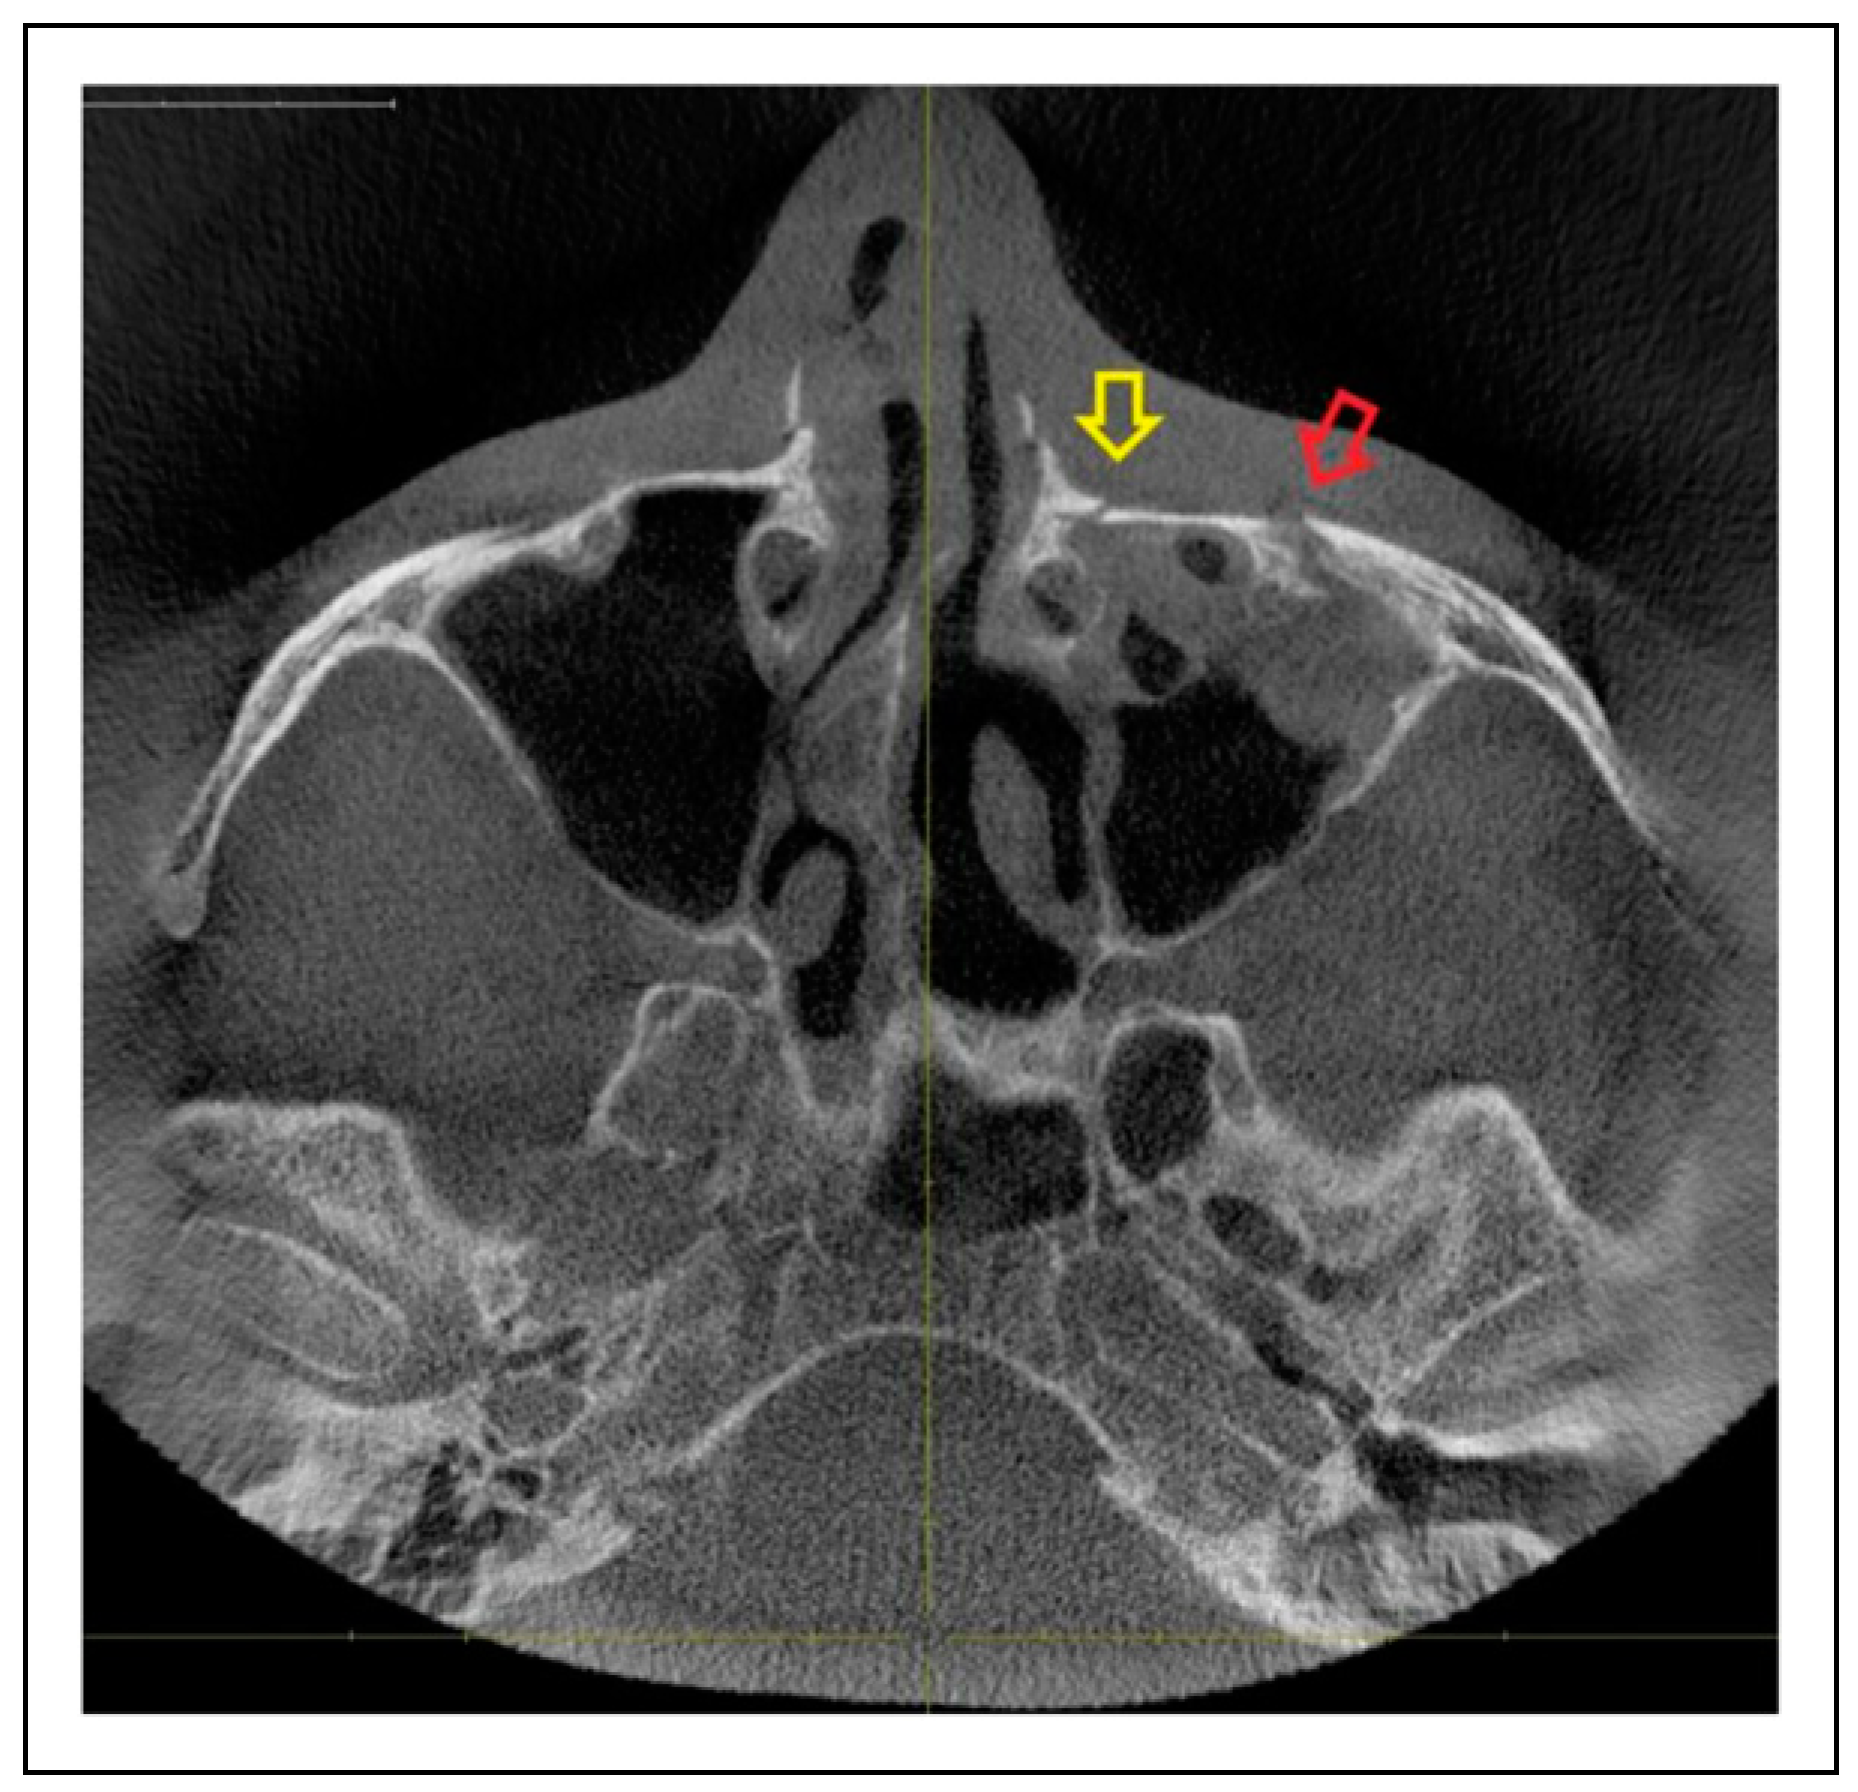

- Zygomaticosphenoidal suture (ZS)—the anterolateral orbital floor

- ZM suture + ZS suture

- ZF suture + ZS suture

- ZM suture + ZF suture + ZS suture